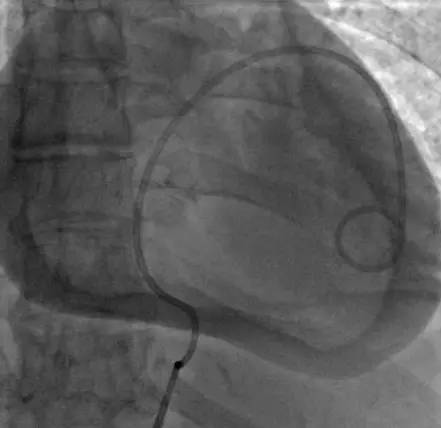

举一反三:心脏压塞致心电图电交替的病例

漫画说介入 | 冠脉穿孔:五大方法自制覆膜支架